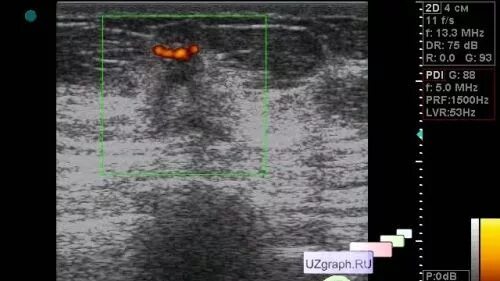

Узи молочных киров